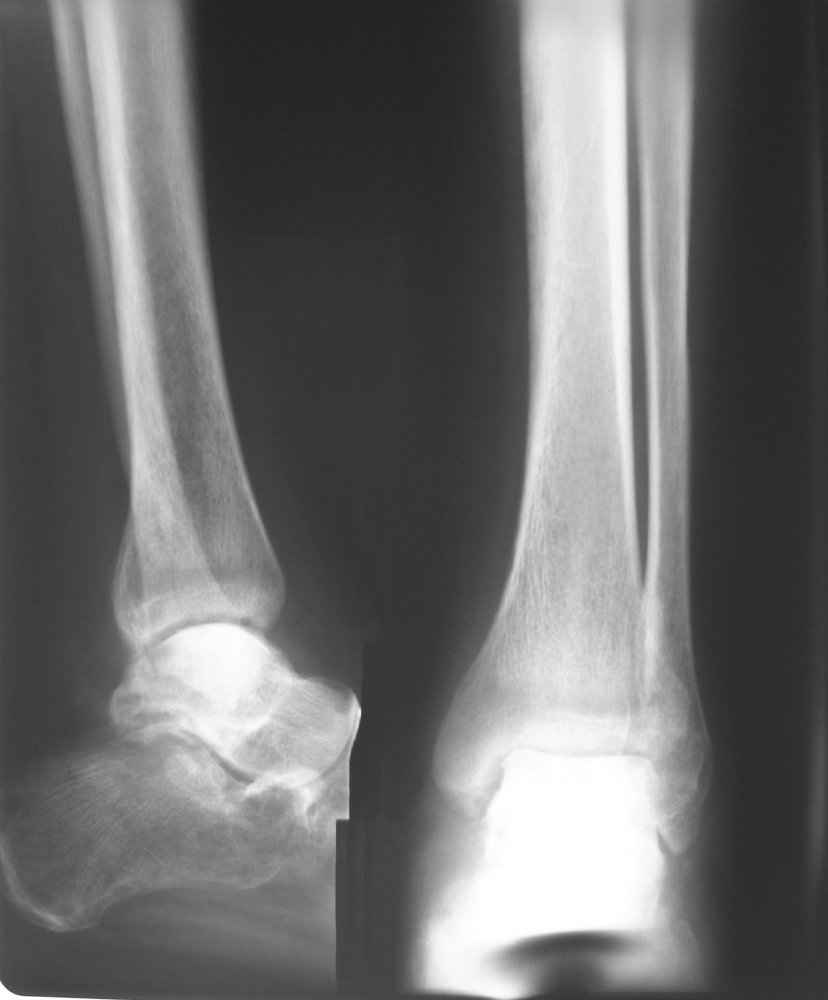

На лечении находится пациент 35 лет. Травма в сентябре 2008 г.- открытый вывих таранной кости

В день травмы ПХО, вправление вывиха, трансартикулярная фиксация. Рана зажила первично. С января нагрузка на конечность. С конца апреля- болевой синдром. На рентгенограммах и КТ признаки ас. некроза таранной кости, артроз подтаранного и голеностопного суставов.